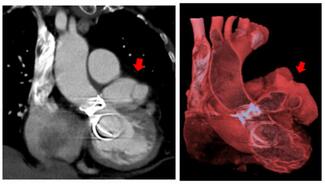

A 39-year-old man with Shone complex presented with acute decompensated heart failure. He had undergone 4 previous sternotomies and a 23-mm Sapien XT transcatheter aortic valve replacement for severe bioprosthetic aortic regurgitation in 2014.